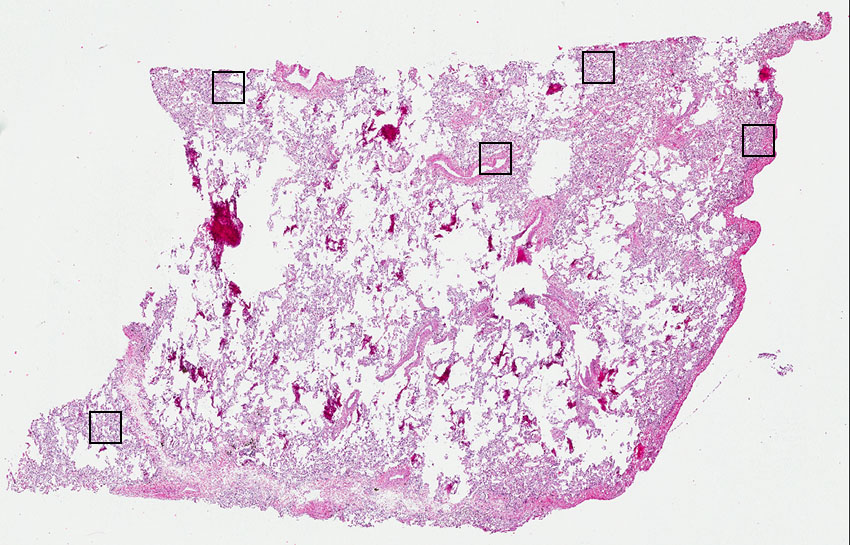

Alveolar cells:

35

Bronchial epithelium:

5

Endothelial cells:

30

Macrophages:

10

Other cell types:

20